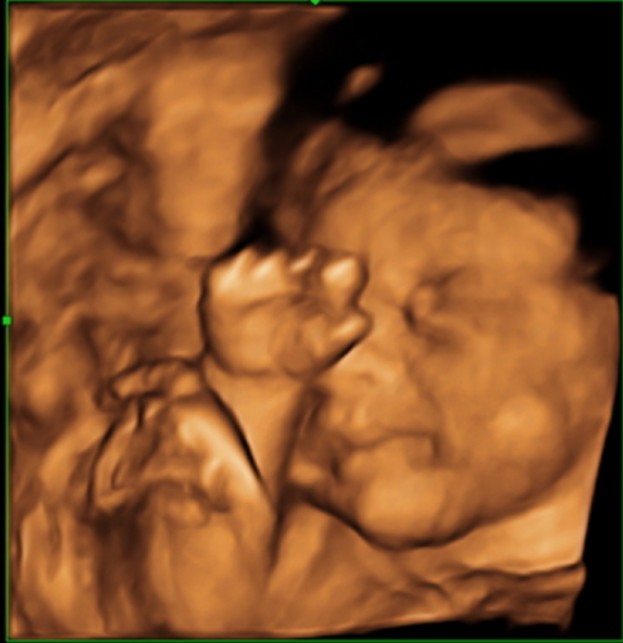

Мы делали и в восторге! 😊 Малыш забавно облизывал ручку, высовывал язычок, улыбался 😍

Скажите, это один и тот же малыш? Просто губки очень разные)) первые две фото очень похожи, прям один в один, и следующие две тоже очень похожи))

😂 😂 😂 Один и тот же, просто этот малыш губки свои шикарные пожимать любит иногда во время сна! 😊 Он это делал в животике и когда родился - так же!

Нам когда сделали УЗИ мы обалдеи, что малыш на фото разный, а потом предположили, что губки поджимает и всё таки родится с пухленькими и бантиком! 😊 Так и вышло